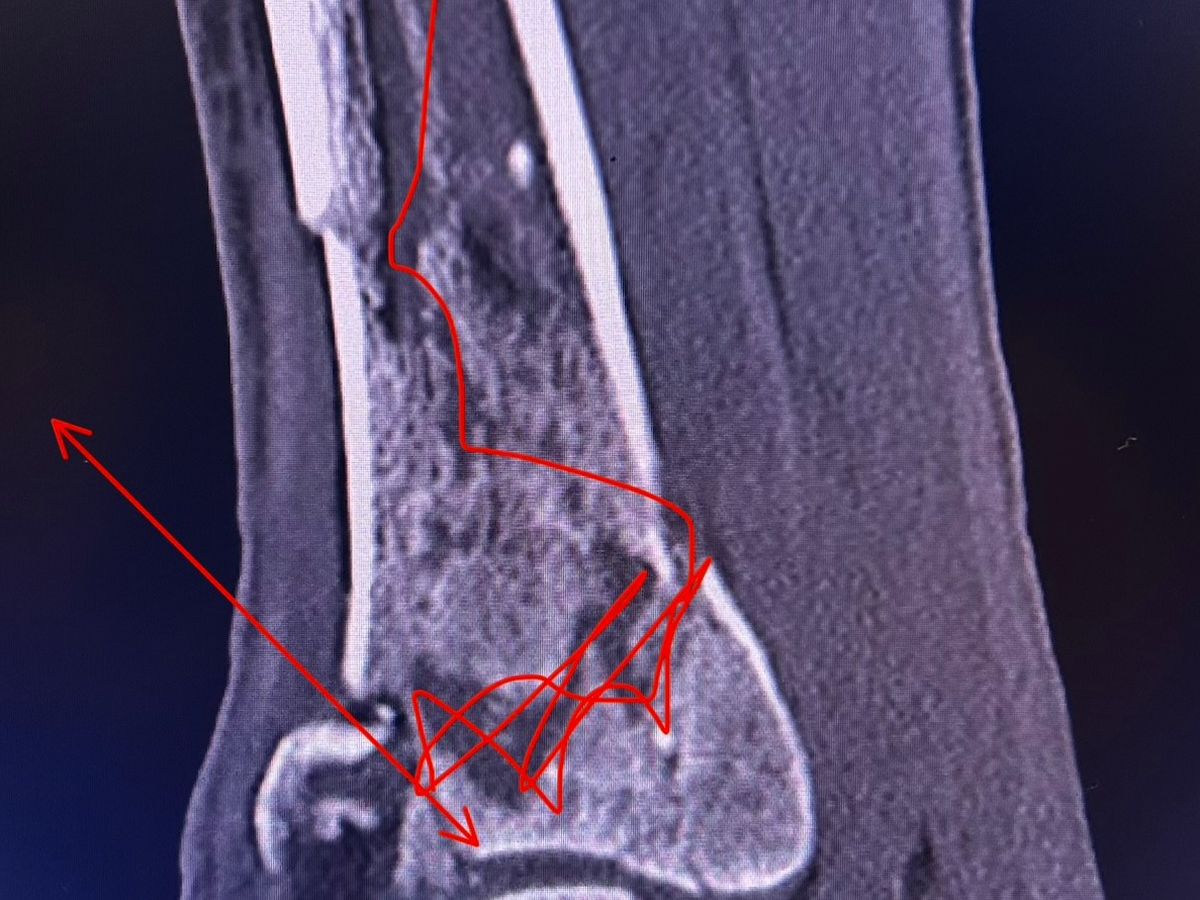

On January 22nd at 10:49 AM, I got the call no one ever wants to receive. It was John, screaming that he had fallen. In that moment, everything stopped. John fell approximately 20–25 feet, causing severe injuries from his left knee down. We are incredibly grateful and beyond blessed that he is alive today, because this situation could have ended very differently.